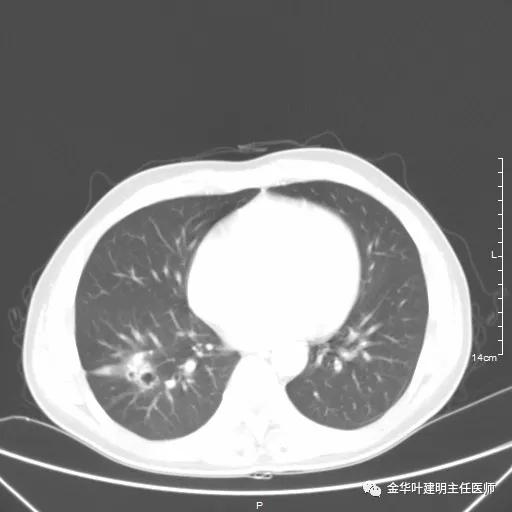

以上为纵隔窗,可见纵隔内未见显著增大的转移性淋巴结。